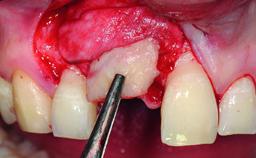

Bone Augmentation | Horizontal|Simultaneous |

Augmentation Materials | Autogenous chips|Xenogenous|Membrane |